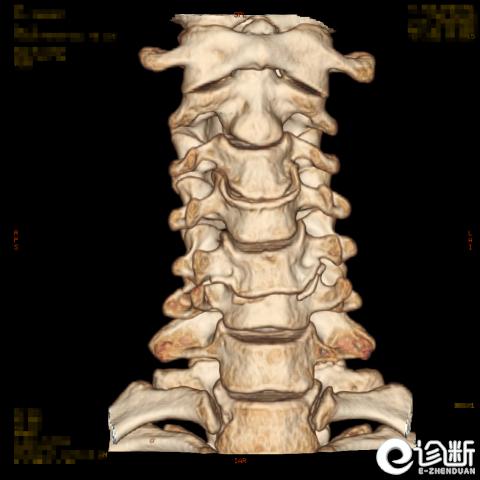

颈椎骨折

CT:显示椎管(骨折碎片可压迫椎管)

根据骨折的水平及位置:C1-Jeferson骨折:前后弓骨折

C1-侧块骨折

C2-Hangman骨折(峡部):Levine分型

C2齿突骨折1型、2型、3型

C3-7骨折: